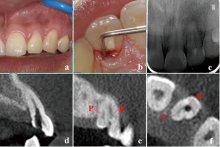

显微根管治疗结合意向性牙再植术治疗双根管上颌侧切牙畸形根面沟1例

Microscopic root canal therapy combined with intentional replantation for the treatment of palatogingival groove in the maxillary lateral incisor with two root canals: A case report

畸形根面沟(palatogingival groove,PGG)是一种位于根面的发育性解剖异常,多见于上颌侧切牙。PGG处牙周组织附着薄弱,易滞留菌斑,引起局部牙周炎症,感染可通过根面沟扩散至牙髓组织,最终导致牙周牙髓联合病变。本文报道了1例因畸形根面沟引起的左上颌侧切牙牙周牙髓联合病变,经显微根管治疗联合意向性牙再植术成功保留患牙,并进行文献回顾,探讨了PGG的诊断要点及治疗方案。

Palatogingival groove (PGG) is a developmental anatomical defect located on the lingual root surface, frequently observed in maxillary lateral incisors. The periodontal attachment in this region is delicate, which makes it vulnerable to plaque accumulation and increases the risk of periodontal inflammation, leading to combined periodontal-endodontic lesions. This article reports a case of a combined periodontal-endodontic lesion in a left maxillary lateral incisor caused by PGG. The tooth was successfully preserved through microscopic root canal therapy combined with intentional replantation. Additionally, a literature review was performed to highlight the key diagnostic features and treatment strategies for PGG.